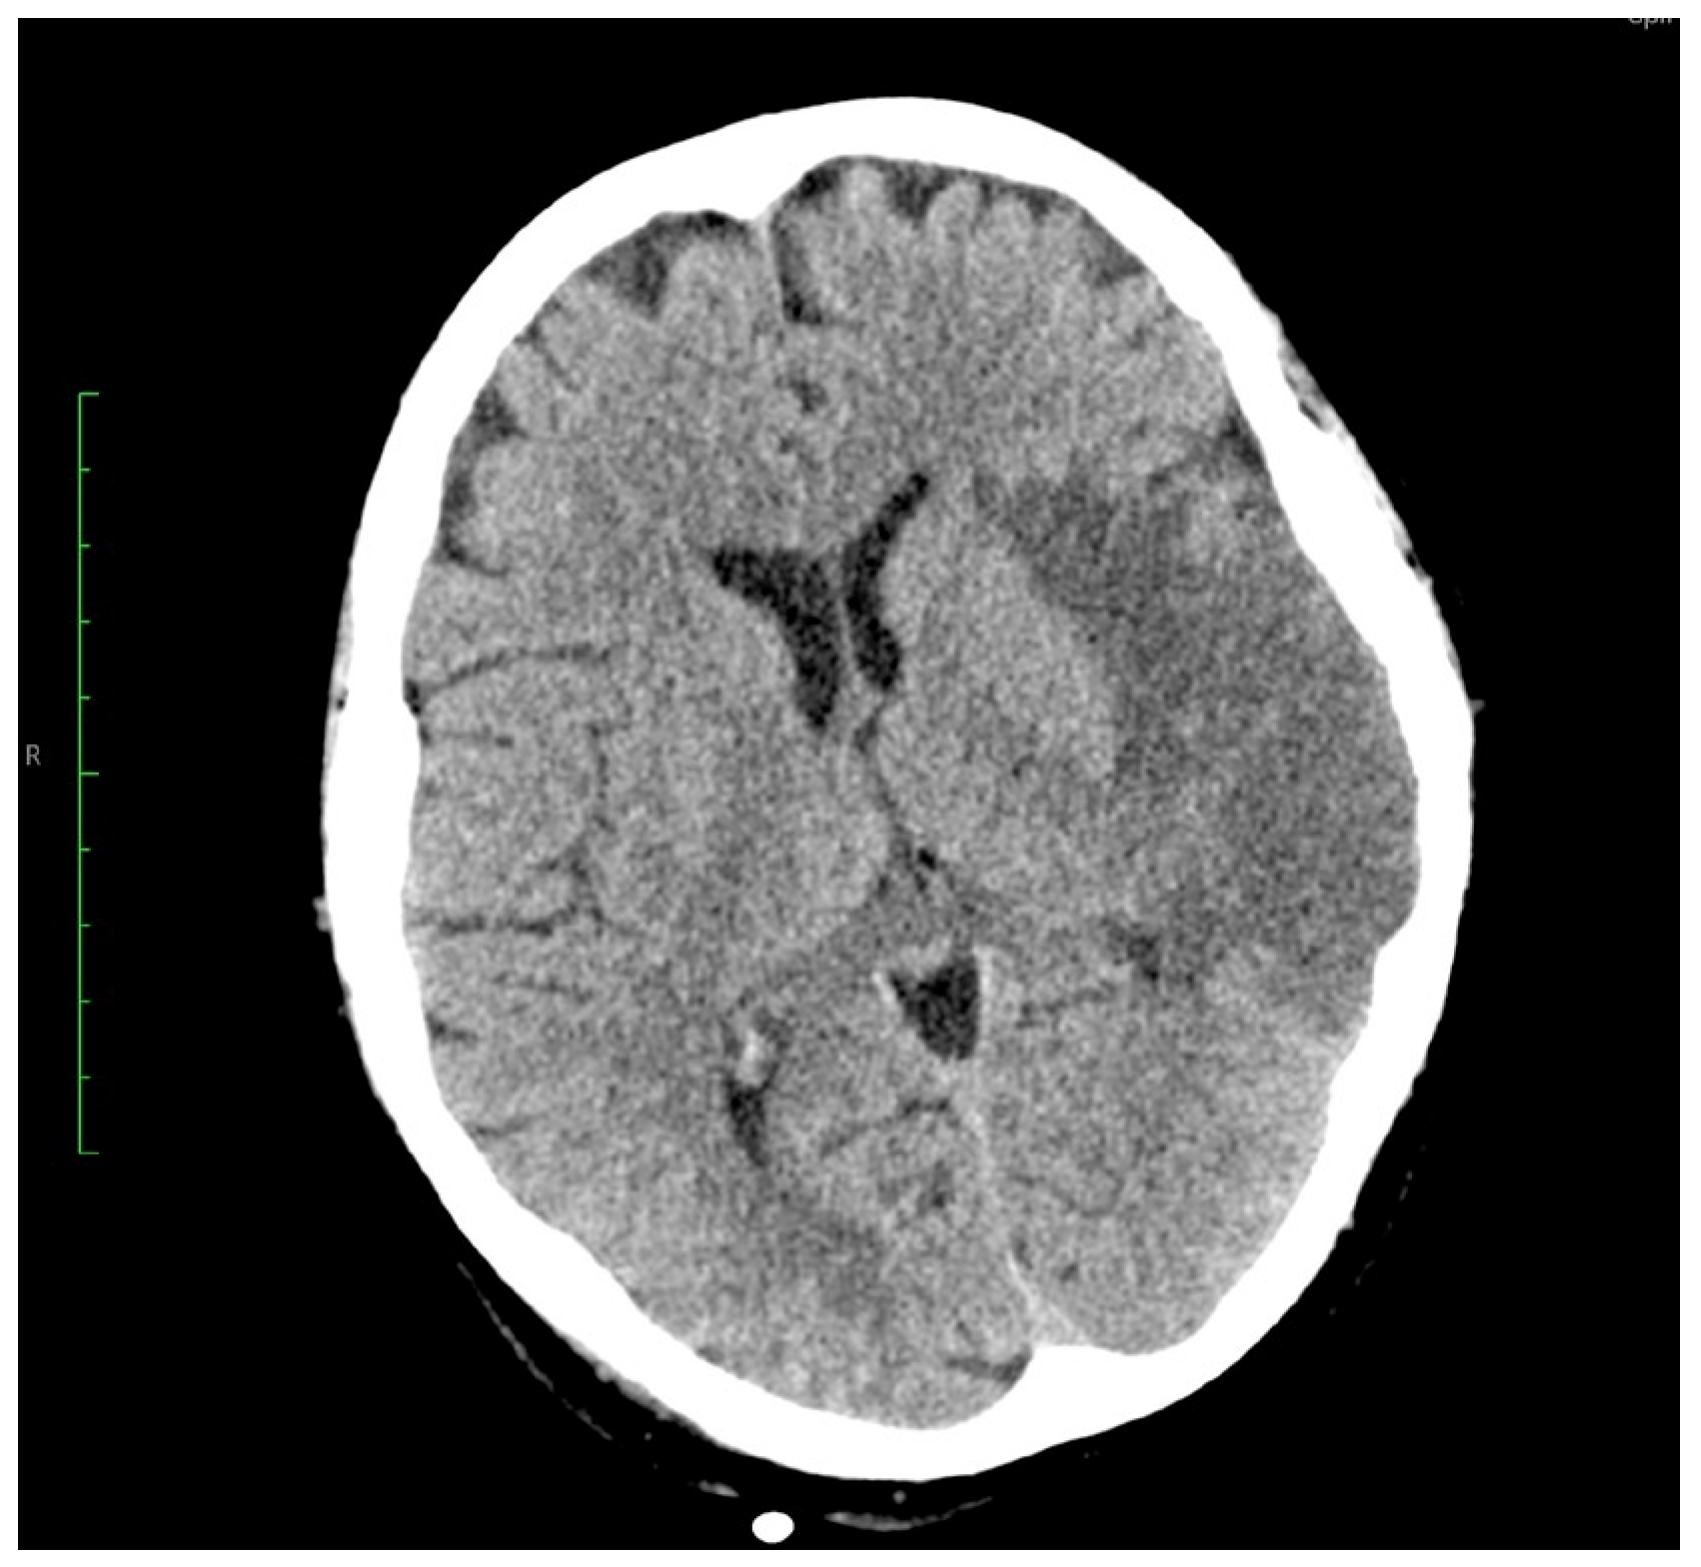

Rare Case of Grade 3 Undifferentiated Pleomorphic Sarcoma in Left Atrium, Mitral Valve, and Papillary Muscle

2. Case Report